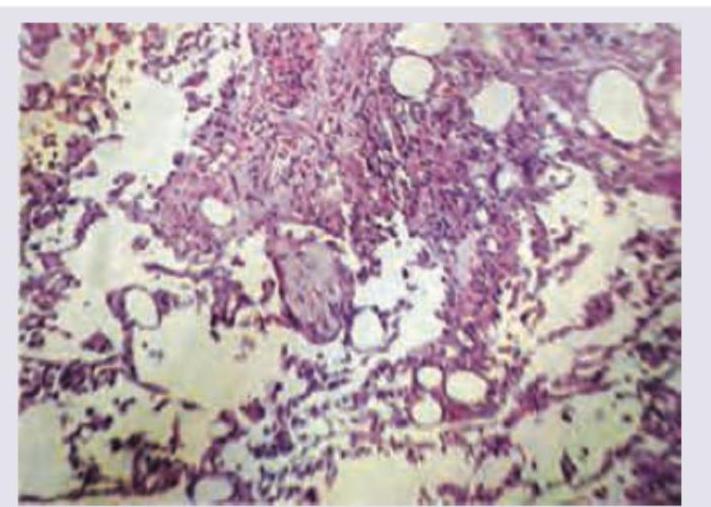

Question 4: A 70-year-old man presents with history of intractable diarrhea. His bone marrow and kidney biopsy are shown below. Which of the following is the most appropriate diagnosis?

- B. Multiple myeloma (Correct Answer)

Explanation: ***Multiple myeloma*** - The combination of intractable diarrhea, bone marrow findings (likely showing **plasma cell proliferation**), and kidney biopsy findings (suggesting **cast nephropathy** or **amyloidosis**) is highly indicative of multiple myeloma [1][3][4]. - **Monoclonal immunoglobulin light chains** produced by plasma cells can cause renal damage and gastrointestinal symptoms like diarrhea [1][2][4]. *Leishmaniasis* - Characterized by **fever**, **splenomegaly**, and **pancytopenia**, with parasites found in macrophages. - While it can affect the bone marrow, it does not typically cause the specific kidney pathology or intractable diarrhea seen in this context. *Lymphoma* - Involves the proliferation of **lymphocytes** and can present with systemic symptoms like fever, weight loss, and lymphadenopathy. - While it can infiltrate the bone marrow and kidneys, it typically does not cause the specific renal casts or amyloid deposition seen in multiple myeloma, nor is intractable diarrhea a primary feature [5]. *Urate nephropathy* - Caused by the deposition of **uric acid crystals** in the renal tubules, leading to acute kidney injury, often in the context of tumor lysis syndrome or gout. - It does not explain the intractable diarrhea or the primary bone marrow pathology of plasma cell proliferation. **References:** [1] Cross SS. Underwood's Pathology: A Clinical Approach. 6th ed. Common Clinical Problems From Blood And Bone Marrow Disease, pp. 616-617. [2] Kumar V, Abbas AK, et al.. Robbins and Cotran Pathologic Basis of Disease. 9th ed. Diseases of White Blood Cells, Lymph Nodes, Spleen, and Thymus, pp. 607-608. [3] Cross SS. Underwood's Pathology: A Clinical Approach. 6th ed. Common Clinical Problems From Blood And Bone Marrow Disease, pp. 617-618. [4] Cross SS. Underwood's Pathology: A Clinical Approach. 6th ed. Common Clinical Problems From Blood And Bone Marrow Disease, pp. 618-619. [5] Kumar V, Abbas AK, et al.. Robbins and Cotran Pathologic Basis of Disease. 9th ed. Diseases of White Blood Cells, Lymph Nodes, Spleen, and Thymus, pp. 606-607.